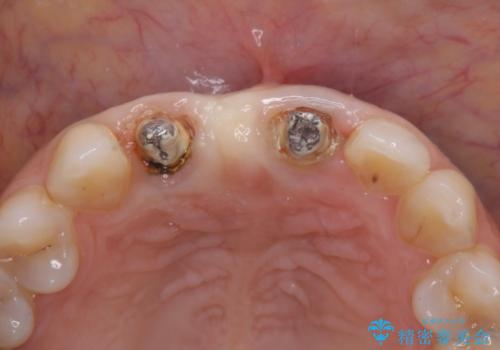

現在装着されているブリッジを除去したところ、歯ぐきよりも上に存在する歯質(縁上歯質)が少なく、土台の形態の悪さや不適合などさまざまな問題があります。

根管治療を行ったのち、歯周外科を行うことで、欠損部の歯ぐきの厚みを出し、縁上歯質を獲得することで、長期的な予後の見込めるブリッジを製作できる環境を整備していきます。